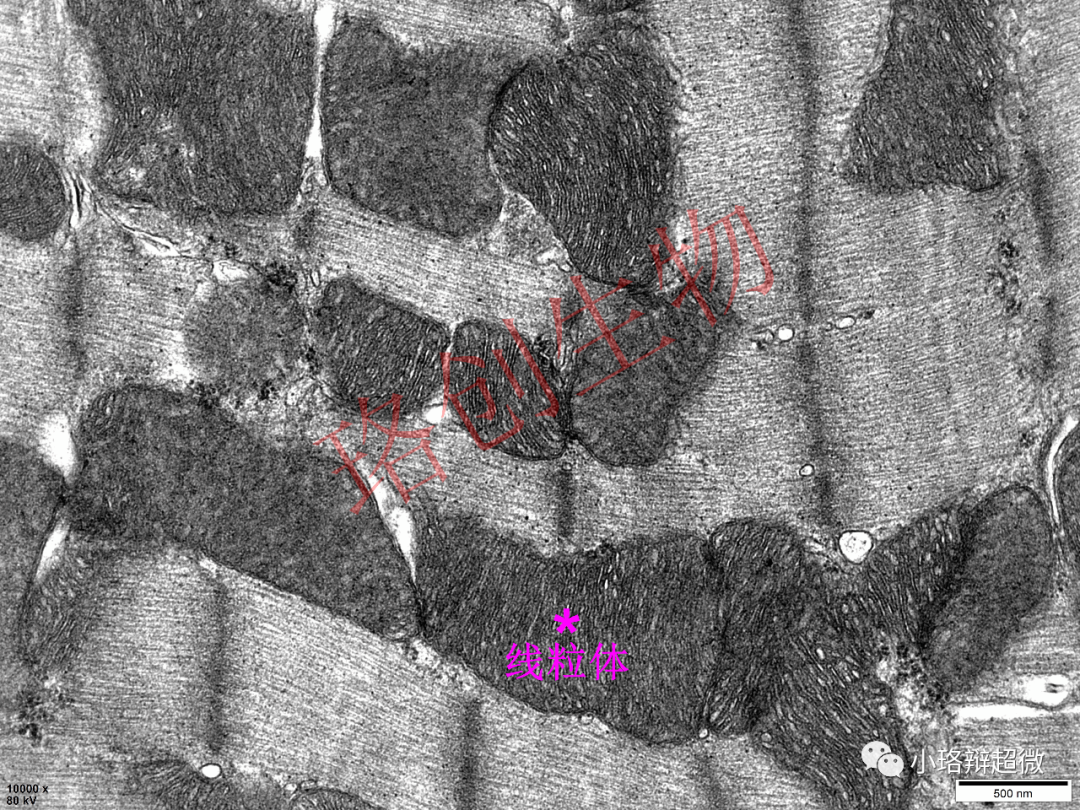

透射电镜下铁死亡发生的典型形态学改变主要为线粒体膜密度增加,线粒体体积减小,伴有嵴的断裂、缺失。

铁死亡组